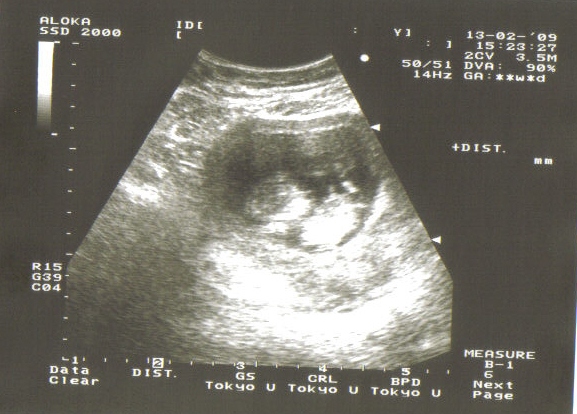

Megvolt az uh.Minden rendben van.CRL:61mm NT:2,1mm.

És egy képecske a kis virgoncról. Kép

Járt keze lába,integetett,emlegette a fenekét!:) Mondtam doki bácsinak remélem kicsit nyugisabb lesz,mint Luca.De azt mondta nem úgy tűnik!:)